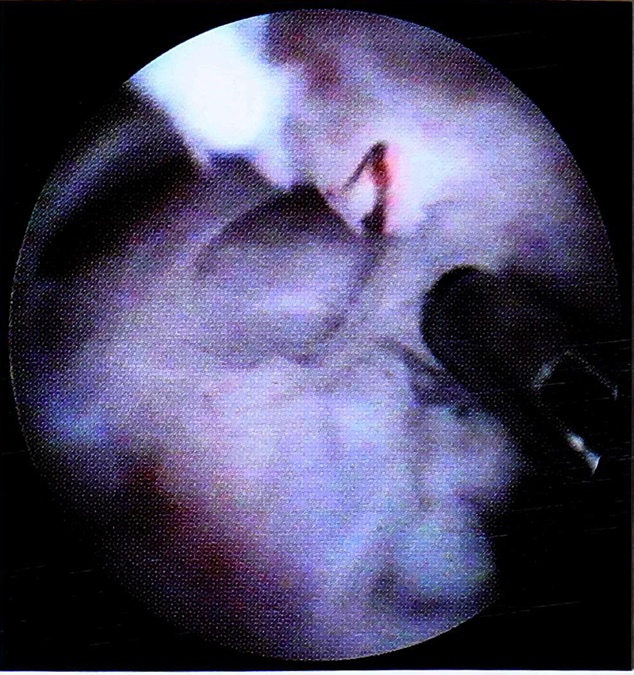

Рис. 8. Иссечение посттравматических спаек.

Используя основные и дополнительные артроскопическиедоступы,, мы получили возможность во всех случаях визуализировать все внутрисуставные структуры,, уточнить ложализащию и степень внутрисуставных повреждении и провести оперативное лечение с помощью артросжопической техники.. Были выполнены следующие виды оперативного лечения: удаление внутрисуставных тел, шейвирование участков повреждения хряща с целью удаления детенержттпвно-виененной хрящевой ткани и сглаживания суставных поверхностей, иссечение множественных посттравматических спаек (рис.. 6-8).